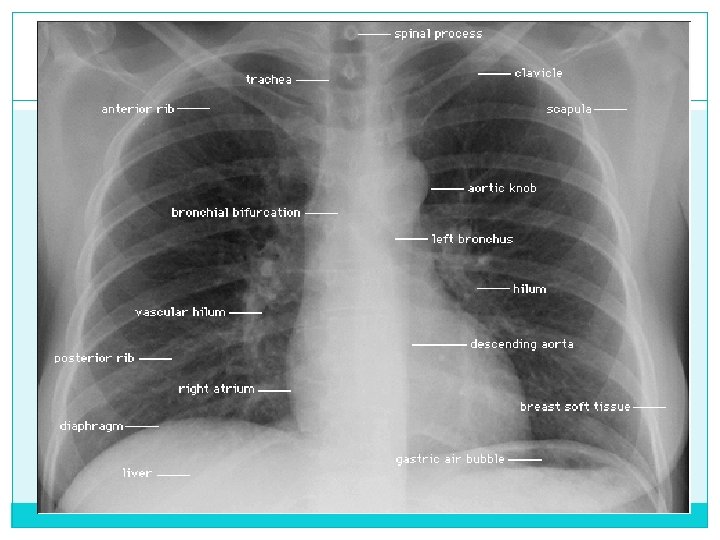

Estructuras del mediastino